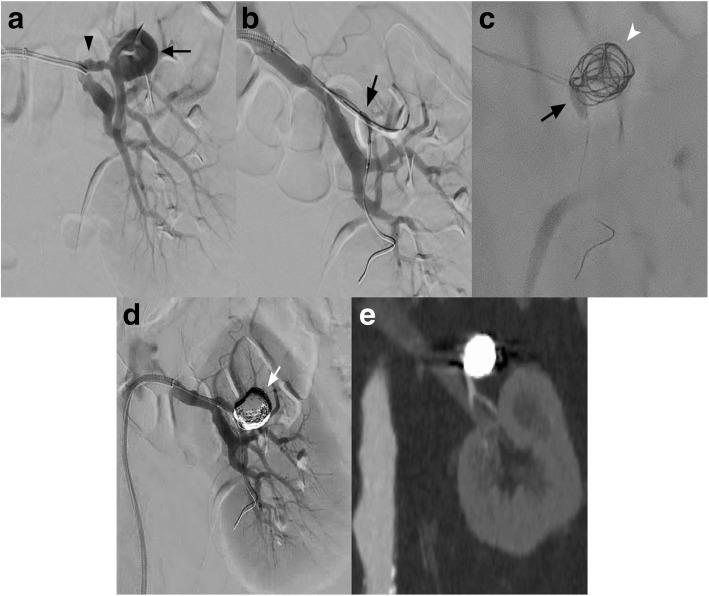

使用颅内Scepter C顺应性闭塞球囊导管对宽颈肾动脉瘤进行球囊辅助弹簧圈栓塞术(BACE)。

Balloon-assisted coil embolization (BACE) of a wide-necked renal artery aneurysm using the intracranial scepter C compliant occlusion balloon catheter.

Intra-procedural remodeling of the aneurysm neck using Balloon Assisted Coil Embolization (BACE) is considered a suitable alternative in challenging cases of visceral artery aneurysms.

We describe the novel use of the Scepter C (MicroVention Terumo, Tustin, CA) compliant double lumen neurovascular occlusion balloon in the treatment of a wide-necked branch TRAA in a patient with a solitary kidney.

真性肾动脉动脉瘤(TRAA)是一种罕见的病理情况,患病率低于1%。当动脉瘤囊等于或超过2厘米时,通常建议对TRAA进行治疗。宽颈和肾动脉主要分支动脉瘤由于存在线圈移位的风险,对传统的血管内线圈栓塞术构成挑战。

在具有挑战性的内脏动脉瘤病例中,使用球囊辅助线圈栓塞术(BACE)对动脉瘤颈部进行术中重塑被认为是一种合适的替代方法。

我们描述了Scepter C(MicroVention Terumo,加利福尼亚州图斯廷)顺应性双腔神经血管闭塞球囊在治疗一名孤立肾患者的宽颈分支TRAA中的新用途。